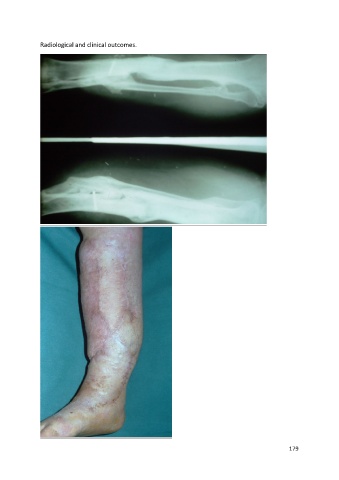

Radiological and clinical outcomes.